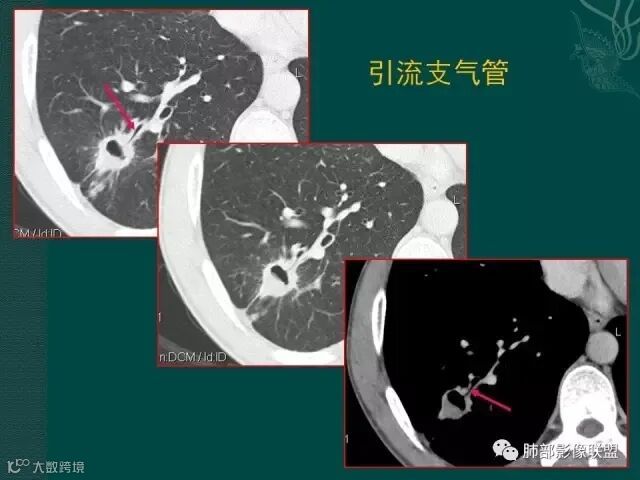

第三个也可以称为空洞,但和第二个不完全相同,壁较薄,内有分隔,我们也称为假性空洞,是支气管活瓣作用形成的,我们也称为假大空。

洞壁的血管,腺癌常见,鳞癌较少,结核罕见

上一个是磨玻璃密度肺癌,边缘清晰,内有分隔,空洞型肺癌伴磨玻璃密度影的,100%为腺癌,很显然这是个假性空洞;

下一个也是肺癌,内有分隔,外下缘箭头所示也是磨玻璃影,这也是腺癌,同时可见叶间裂有转移灶。